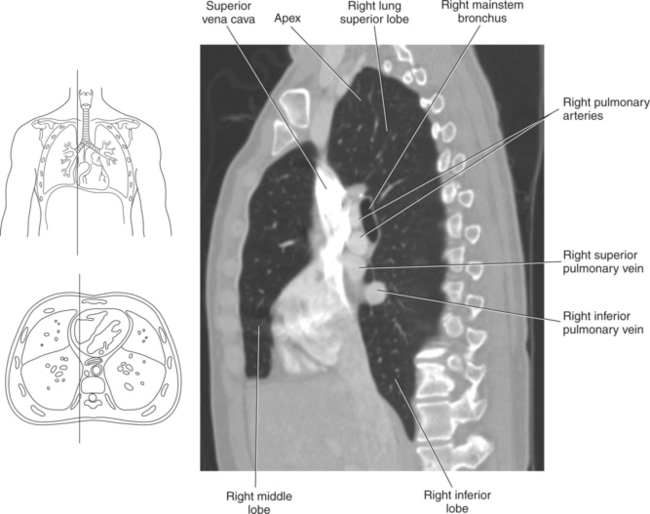

The lungs are the organs of respiration, where gaseous exchange occurs between the respiratory air and blood. They are composed of a spongelike material, the parenchyma, and surrounded by a layer of serous membrane. The large conical-shaped lungs extend up to or slightly above the level of the first rib at their apex and down to the dome of the diaphragm at their wide concave-shaped bases or diaphragmatic surfaces (Figure 6.9). Each lung has a mediastinal or medial surface that is apposed to the mediastinum, and a costal surface that is apposed to the inner surface of the rib cage. Each lung also has an inferior, anterior, and posterior border. The inferior border extends into the costodiaphragmatic recess of the pleural cavity, and the anterior border of each lung extends into the costomediastinal recess of the pleural cavity (Figure 6.10). Two prominent angles can be identified at the medial and lateral edges of the lung bases. The medial angle is termed the cardiophrenic sulcus, and the lateral angle is termed the costophrenic sulcus (Figure 6.11 and 6.12). The lungs are divided into lobes by fissures that are lined by pleura and may extend as far as the hilum (Figure 6.13). The right lung has three lobes (superior [upper], middle, and inferior [lower]), whereas the left lung has just superior (upper) and inferior (lower) lobes (Figures 6.6 and 6.11 through 6.13). The inferior lobe of the right lung is separated from the middle and superior lobes by the oblique fissure, termed oblique because of its posterosuperior to anteroinferior course. Separating the middle lobe from the superior lobe is the horizontal fissure (Figures 6.9 and 6.14, A). An oblique fissure also separates the superior and inferior lobes of the left lung (Figure 6.11). The left lung has a large notch on the medial surface of its superior lobe called the cardiac notch and a tonguelike projection off its inferoanterior surface termed the lingula. Each lung has an opening on the medial surface termed the hilum (Figures 6.14 through 6.16). This opening acts as a passage for mainstem bronchi, blood vessels, lymph vessels, and nerves to enter or leave the lung and is commonly referred to as the root of the lung.

Blood travels to and from the heart through the great vessels, which include the aorta, pulmonary arteries and veins, and superior and inferior venae cavae (Figures 6.54 and 6.55). The aorta is the largest artery of the body and can be divided into the ascending aorta, aortic arch, and descending aorta. The ascending aorta begins at the base of the left ventricle at the level of the sternal angle, then curves superiorly and posteriorly as the aortic arch over the root of the left lung. The top of the aortic arch is approximately at T3 (Figures 6.56 and 6.57). The arch continues as the descending aorta posterior to the left bronchus and pulmonary trunk, on the left side of the vertebral body of T4 (Figures 6.58 and 6.59). The descending aorta passes slightly anterior and to the left of the vertebral column as it descends through the thoracic and abdominal cavities (Figure 6.60). While in the thoracic cavity, the descending aorta is commonly called the thoracic aorta, and while in the abdominal cavity, it is called the abdominal aorta. The pulmonary trunk is the origin of the right and left pulmonary arteries and lies entirely within the pericardial sac. It arises from the right ventricle and ascends in front of the ascending aorta, courses posteriorly and to the left, where it bifurcates at the level of the sternal angle (T4) into the right and left pulmonary arteries (Figures 6.61 through 6.63). The pulmonary trunk is attached to the aortic arch by a fibrous cord called the ligamentum arteriosum, the remnant of an important fetal blood vessel (ductus arteriosus) that links the pulmonary and systemic circuits during fetal development (Figures 6.54 and 6.61). The right pulmonary artery courses laterally, posterior to the ascending aorta and superior vena cava, and anterior to the esophagus and right mainstem bronchus, to the hilum of the right lung. At the root of the right lung, the right pulmonary artery divides into two branches, with the lower branch supplying the middle and inferior lobes and the upper branch supplying the superior lobe (Figures 6.61 through 6.64). The left pulmonary artery, shorter and smaller than the right, is also the most superior of the pulmonary vessels. It travels horizontally, arching over the left mainstem bronchus, and enters the hilum of the left lung just superior to the left mainstem bronchus (Figures 6.61 through 6.64). Within the lungs, each pulmonary artery descends posterolateral to the main bronchus and divides into lobar and segmental arteries, continuing to branch out and to follow along with the smallest divisions of the bronchial tree (Figures 6.61 and 6.64). Located inferior to the pulmonary arteries are the four pulmonary veins, two each (superior and inferior) extending from each lung to enter the left atrium (Figures 6.54, 6.55, 6.61, and 6.64 through 6.68). They commence in a capillary network along the walls of the alveoli, where they are continuous with the capillaries of the pulmonary arteries. The venous capillaries merge to form small vessels that unite successively to eventually form a single trunk for each lobe: three for the right and two for the left lung. Frequently the trunk from the middle lobe of the right lung unites with the trunk from the upper lobe, forming just two trunks on the right side prior to entering the left atrium. The right superior pulmonary vein collects blood from the upper lobe segments of the right lung and passes anterior and inferior to the right pulmonary artery, behind the superior vena cava. The right inferior pulmonary vein receives blood from the right lower lobes of the lung and crosses behind the right atrium to the left atrium (Figures 6.61 and 6.69 through 6.71). The left superior pulmonary vein receives blood from the left upper lobe of the left lung and courses anterior and inferior to the left main bronchus as it enters the left atrium. The left inferior pulmonary vein drains the inferior lobe of the left lung and passes toward the left atrium anterior to the bronchi (Figures 6.61 and 6.72 through 6.74). The pulmonary veins course more horizontally than the pulmonary arteries and are ultimately oriented toward the left atrium. At the root of the lungs, the pulmonary veins are anterior to the pulmonary arteries, which are anterior to the bronchus. While within the lungs, the branches of the pulmonary arteries are anterior to the bronchi, which are anterior to the pulmonary veins. The superior and inferior venae cavae are the largest veins of the body. The superior vena cava is formed by the junction of the brachiocephalic veins, posterior to the right first costal cartilage, and carries blood from the thorax, upper limbs, head, and neck (Figure 6.24). As it travels inferiorly, it is located posterior and lateral to the ascending aorta before entering the upper portion of the right atrium (Figures 6.54 through 6.59). The inferior vena cava is formed by the junction of the common iliac veins in the pelvis and ascends the abdomen to the right of the abdominal aorta and anterior to the vertebral column. It passes through the caval hiatus of the diaphragm and almost immediately enters the inferior portion of the right atrium (Figures 6.75 and 6.76).